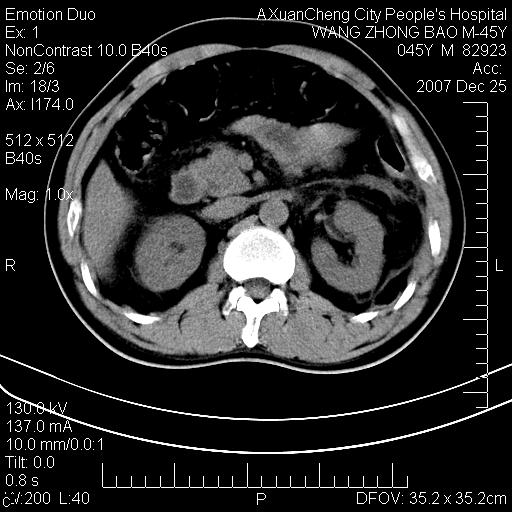

以下是引用qiuleiyu在2007-12-25 18:14:00的发言:[br]胰腺增大,周边渗出改变,肾前筋膜明显增厚,示少量积液.胆囊壁毛糙,周边少许渗出,胆总管壁厚,异常强化,然扩张不明显.结合病程急短;考虑;胆管炎,胆囊炎,胆源性胰腺炎可能大,请结合实验室检查及随访.

以下是引用lisihao在2007-12-25 14:23:00的发言:[br]急性水肿型胰腺炎[br]依据:1、胰腺弥漫性肿大,边缘稍毛糙;[br] 2、双侧肾周筋膜增厚,尤以左侧为甚(重要征象)[br] 3、双侧后胸膜增厚(刺激性炎症);[br] 4、结合病史,查血尿淀粉酶应该可以确诊。